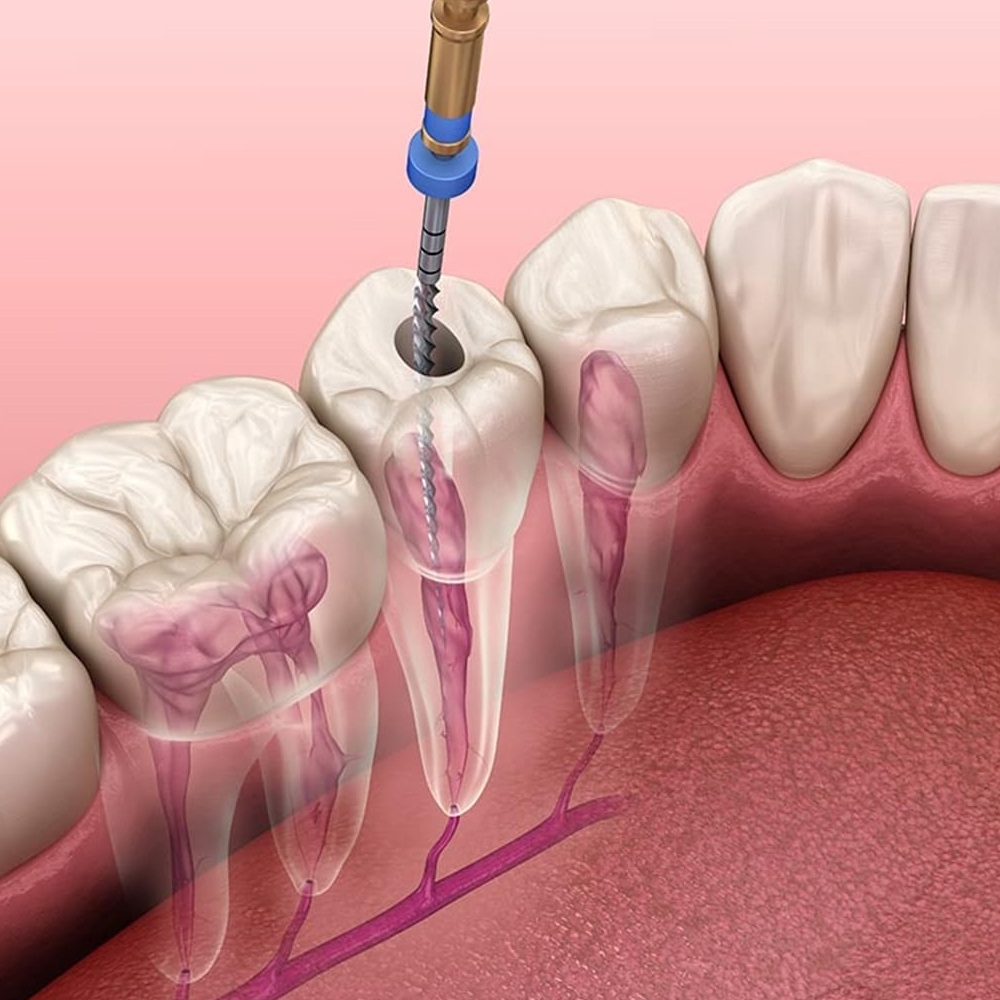

Periodontitis; diş ve dişi destekleyen dokuların (periodontal ligament, sement, alveol kemiği) yıkımıyla karakterize iltihapsal bir hastalıktır. Diş eti iltihabı, alveol kemiğine (çene kemiği) kadar ilerlemiştir. Periodontitisin temel nedeni; bakteri plağıdır ve mekanik olarak tedavi edilebilir. Ancak genetik, çevresel ve sistematik faktörler de hastalığın oluşmasında etken olabilir. Sistemik faktörler içinde diabet, kalp damar hastalıkları, epilepsi, down sendromu, AIDS ve kan hastalıkları sayılabilir.

Dişhekimleri dişetlerinin genel görünümünden şüphelendikleri zaman ‘periodontal sonda’ adı verilen bir alet ile diş ile dişeti arasındaki dişeti cebinin boyunu ölçerler. Ayrıca dişlerin etrafındaki kemik dokusunu değerlendirmek için röntgen filmler alınabilir. Böylece dişeti hastalıkları teşhis edilir.

Periodontal tedavinin ana amacı ise umutsuz gibi görünen sağlıksız dişleri ağızda tutmaktır. Hastalığın tipi ve şiddetine göre değişik tedavi yöntemleri uygulanabilir. Bunlar; öncelikle ağız hijyeni eğitimi, diş taşı temizliği, kök yüzeyi düzleştirilmesi, rejeneratif, rekonstrüktif ve mukogingival operasyonlar olarak özetlenebilir. Aynı zamanda yüksek gülme hattı olan bireylerin diş eti estetiğini sağlamak da, periodontal tedavi kapsamındadır. Hastalığın tipi ve şiddeti, hastanın alışkanlıkları, hekimi ile yapacağı işbirliği, ağız hijyeninin standardı, tedavi planlaması ve başarısını doğrudan etkiler.